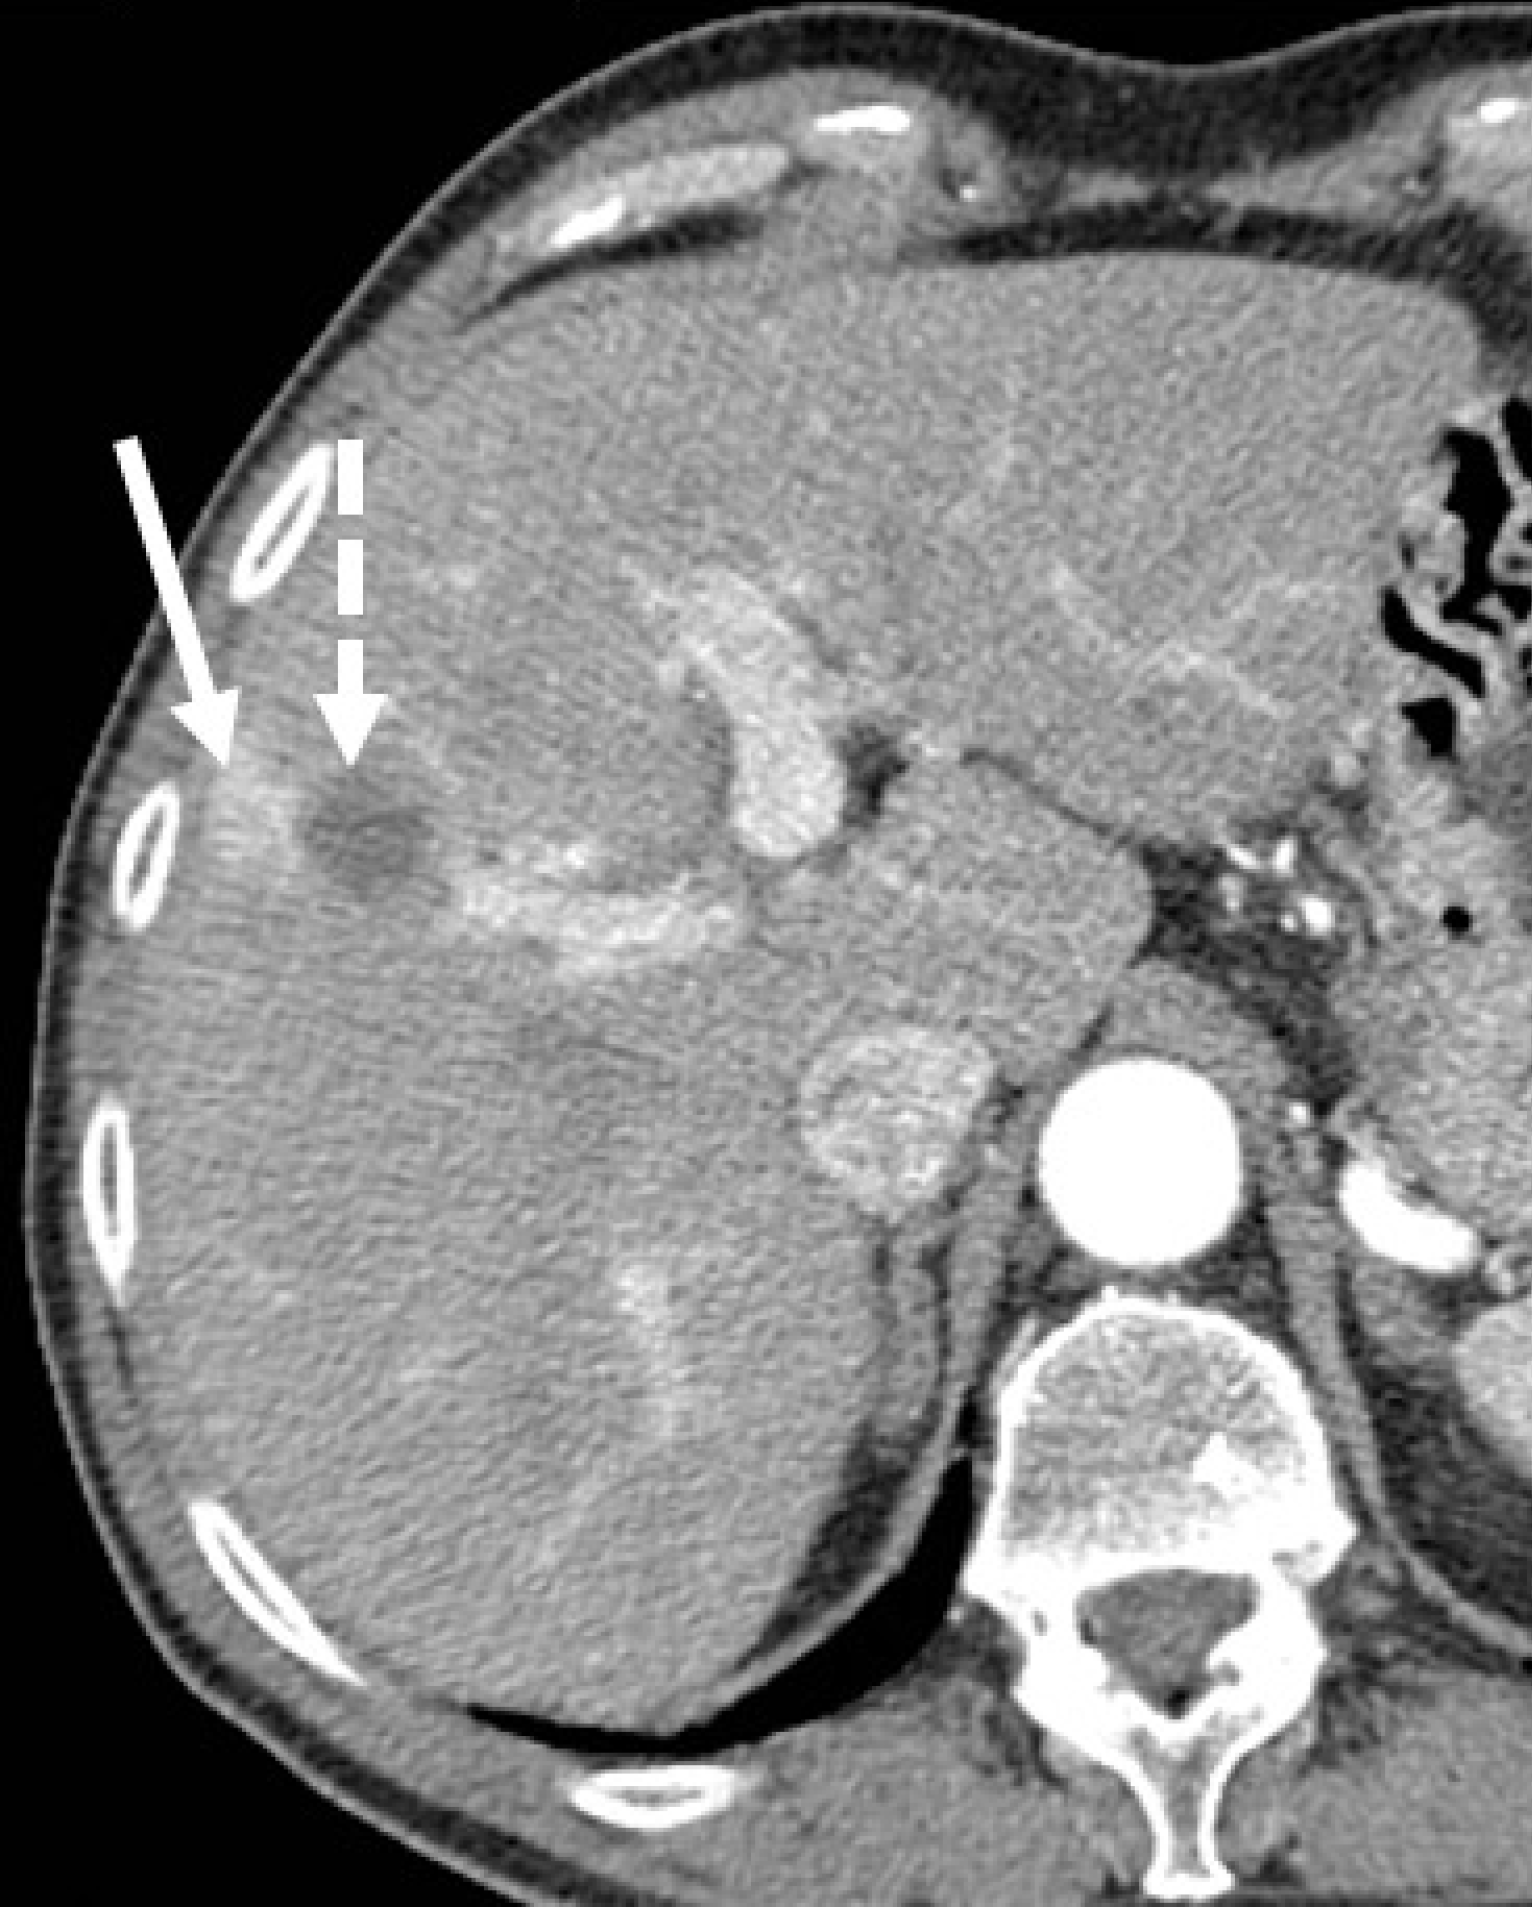

Figure 6 Perfusion alteration after hepatocellular carcinoma radiofrequency ablation in a 62-year-old man with hepatitis C virus-related cirrhosis.

Hepatic arterial phase computed tomography (CT) obtained 1 month after treatment shows an enhancing area (solid arrow) lateral to the ablated zone (dotted arrow). This area showed no venous wash-out and disappeared on subsequent CT follow-up (images not shown).